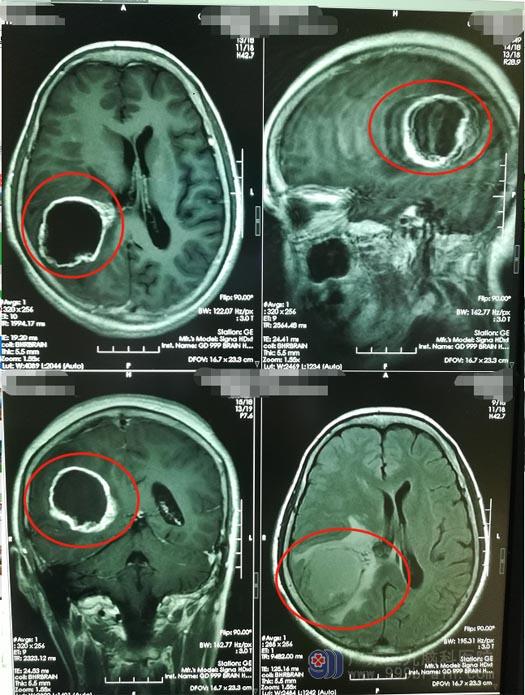

李阿姨入住广东三九脑科医院神经外五科后,进一步的头颅MRI显示:右侧颞顶叶占位性病变侵犯右侧侧脑室后角室膜,考虑偏高级别肿瘤,胶质母细胞瘤可能性大。

医院副院长、神经外五科主任鲁明认为患者的右侧颞顶叶占位考虑胶质瘤,肿瘤体积大,约50mm×39mm×47mm,手术指证明确,可以择期手术。术前准备妥当后,在全麻下行“右侧颞顶叶、侧脑室后角占位性病变切除术”,经过5个小时的奋战,顺利完成手术。术后MRI显示肿瘤已全部切除。